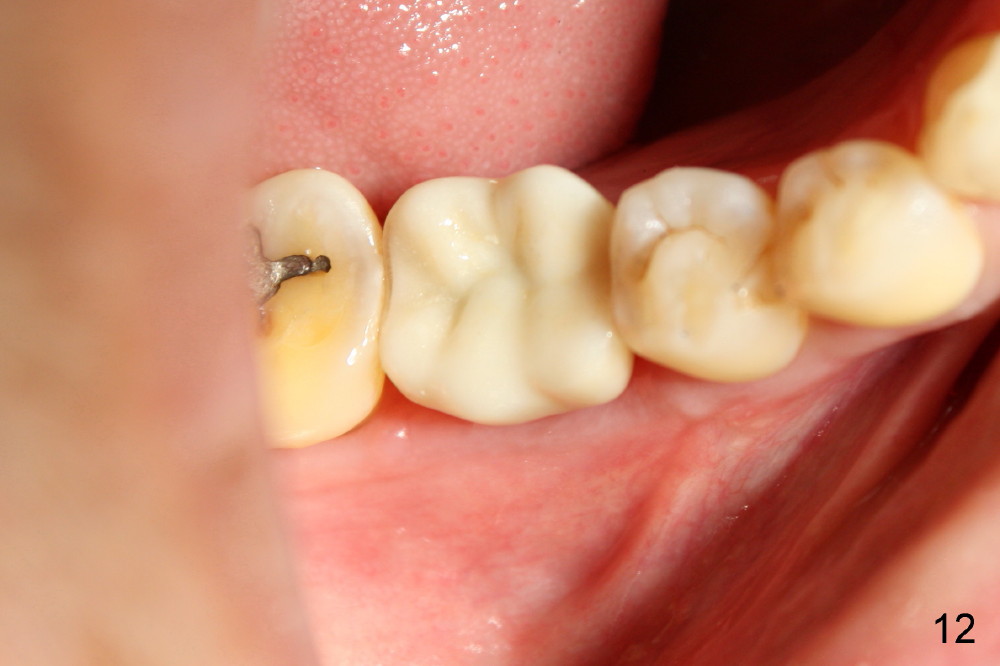

The infection may be related to chronic infection at the tooth #9. The latter is extracted, but the infection at the site of #30 does not resolve (Fig.5,6). The buccal flap is raised to reveal granulation tissue distobuccal to the implant (Fig.7). Bony defect and implant thread exposure are shown after debridement (Fig.8). Irradiated cancellous bone graft is placed to the defect (Fig. 9, Rocky Mountain Tissue Bank). The flap is closed with relative tension free. The definitive crown is temporarily cemented. The graft is exposed with no infection 2 week post grafting (Fig.10). The distobuccal defect appears to have healed 5 months post grafting (Fig.11) and the crown is permanently cemented (Fig.12). There is no buccal bone resorption, probably associated with immediate implantation. The patient remains asymptomatic 13 months postop.